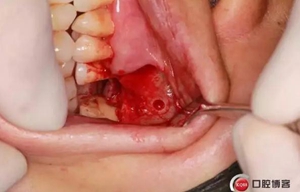

改良式外提升工具盒-外提 科貿(mào)嘉友收錄

大家好,我是梁老師的助理小依。由于梁老師每天手術(shù)檔期安排較滿,加上經(jīng)常出差講課,沒有時(shí)間整理病例 。為了方便大家更及時(shí)的了解梁老師最新手術(shù)動(dòng)態(tài),以后將由我為大家整理并推送梁老師最新經(jīng)典案例。案例文字旁白少,但圖片會(huì)盡量完整展示手術(shù)全過程,供大家學(xué)習(xí)參考。有任何問題,可以留言,梁老師會(huì)親自為大家解答。感謝大家對梁老師的支持和關(guān)注!

六個(gè)月之后